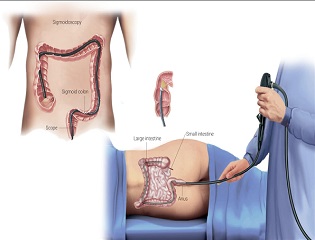

❈ What is a colonoscopy?

Colonoscopy lets your doctor examine the lining of your large intestine (colon) for abnormalities by inserting a thin flexible tube, as thick as your finger, into your anus and slowly advancing it into the rectum and colon. This instrument, called a colonoscope, has its own lens and light source and it allows your doctor to view images on a video monitor.

❈ Why is colonoscopy recommended?

The procedure is indicated in the following

- Unexplained changes in bowel habits.

- Bleeding from the back passage.

- Weight loss.

- Chronic constipation or chronic diarrhoea.

- History of polyps.

- Screening for cancer.

❈ What preparations are required?

Your doctor will tell you what dietary restrictions to follow and what cleansing routine to use. In general, the preparation consists of limiting your diet to clear liquids the day before and consuming either a large volume of a special cleansing solution or special oral laxatives. The colon must be completely clean for the procedure to be accurate and comprehensive, so be sure to follow your doctor’s instructions carefully.

❈ Can I take my current medications?

Most medications can be continued as usual, but some medications can interfere with the preparation or the examaination. Inform your doctor about medications you’re taking, particularly aspirin products, arthritis medications, anticoagulants (blood thinners such as warfarin or heparin), clopidogrel, insulin or iron products. Also, be sure to mention allergies you have to medications.

❈ What happens during colonoscopy?

Colonoscopy is well-tolerated and rarely causes much pain. You might feel pressure, bloating or cramping during the procedure. Typically, your doctor will give you a sedative or painkiller to help you relax and better tolerate any discomfort. You will lie on your side or back while your doctor slowly advances a colonoscope along your large intestine to examine the lining. Your doctor will examine the lining again as he or she slowly withdraws the colonoscope. The procedure itself usually takes less than 30 minutes, although you should plan on two to three hours for waiting, preparation and recovery. In some cases, the doctor cannot pass the colonoscope through the entire colon to where it meets the small intestine. Your doctor will advise you whether any additional testing is necessary.

❈ What if the colonoscopy shows something abnormal?

If your doctor thinks an area needs further evaluation, he or she might pass an instrument through the colonoscope to obtain a biopsy (a small sample of the colon lining) to be analyzed. Biopsies are used to identify many conditions, and your doctor will often take a biopsy even if he or she doesn’t suspect cancer. If colonoscopy is being performed to identify sites of bleeding, your doctor might control the bleeding through the colonoscope by injecting medications or by cauterization (sealing off bleeding vessels with heat treatment) or by use of small clips. Your doctor might also find polyps during colonoscopy, and he or she will most likely remove them during the examination. These procedures don’t usually cause any pain.

❈ What are polyps and why are they removed?

Polyps are abnormal growths in the colon lining that are usually benign (noncancerous). They vary in size from a tiny dot to several inches. Your doctor can’t always tell a benign polyp from a malignant (cancerous) polyp by its outer appearance, so he or she will usually remove polyps for analysis. Because cancer begins in polyps, removing them is an important means of preventing colorectal cancer.

❈ How are polyps removed?

Your doctor may destroy tiny polyps by fulguration (burning) or by removing them with wire loops called snares or with biopsy instruments. Your doctor will use a technique called “snare polypectomy” to remove larger polyps. Your doctor will pass a wire loop through the colonoscope and remove the polyp from the intestinal wall using an electrical current. You should feel no pain during the polypectomy.

❈ What happens after a colonoscopy?

You will be monitored until most of the effects of the sedatives have worn off. You might have some cramping or bloating because of the air introduced into the colon during the examination. This should disappear quickly when you pass gas. Your physician will explain the results of the examination to you, although you’ll probably have to wait for the results of any biopsies performed. If you have been given sedatives during the procedure, someone must drive you home and stay with you. Even if you feel alert after the procedure, your judgment and reflexes could be impaired for the rest of the day. You should be able to eat after the examination, but your doctor might restrict your diet and activities, especially after polypectomy. Your doctor will advise you on this.

❈ What are the possible complications of colonoscopy?

Colonoscopy and polypectomy are generally safe when performed by doctors who have been specially trained and are experienced in these procedures. One possible complication is a perforation, or tear, through the bowel wall. Bleeding might occur at the site of biopsy or polypectomy, but it’s usually minor. Bleeding can stop on its own or be controlled through the colonoscope; it rarely requires follow-up treatment. Some patients might have a reaction to the sedatives or complications from heart or lung disease. Although complications after colonoscopy are uncommon, it’s important to recognize early signs of possible complications. Contact your doctor if you notice severe abdominal pain, fever and chills, or rectal bleeding. Note that bleeding can occur several days after the procedure.